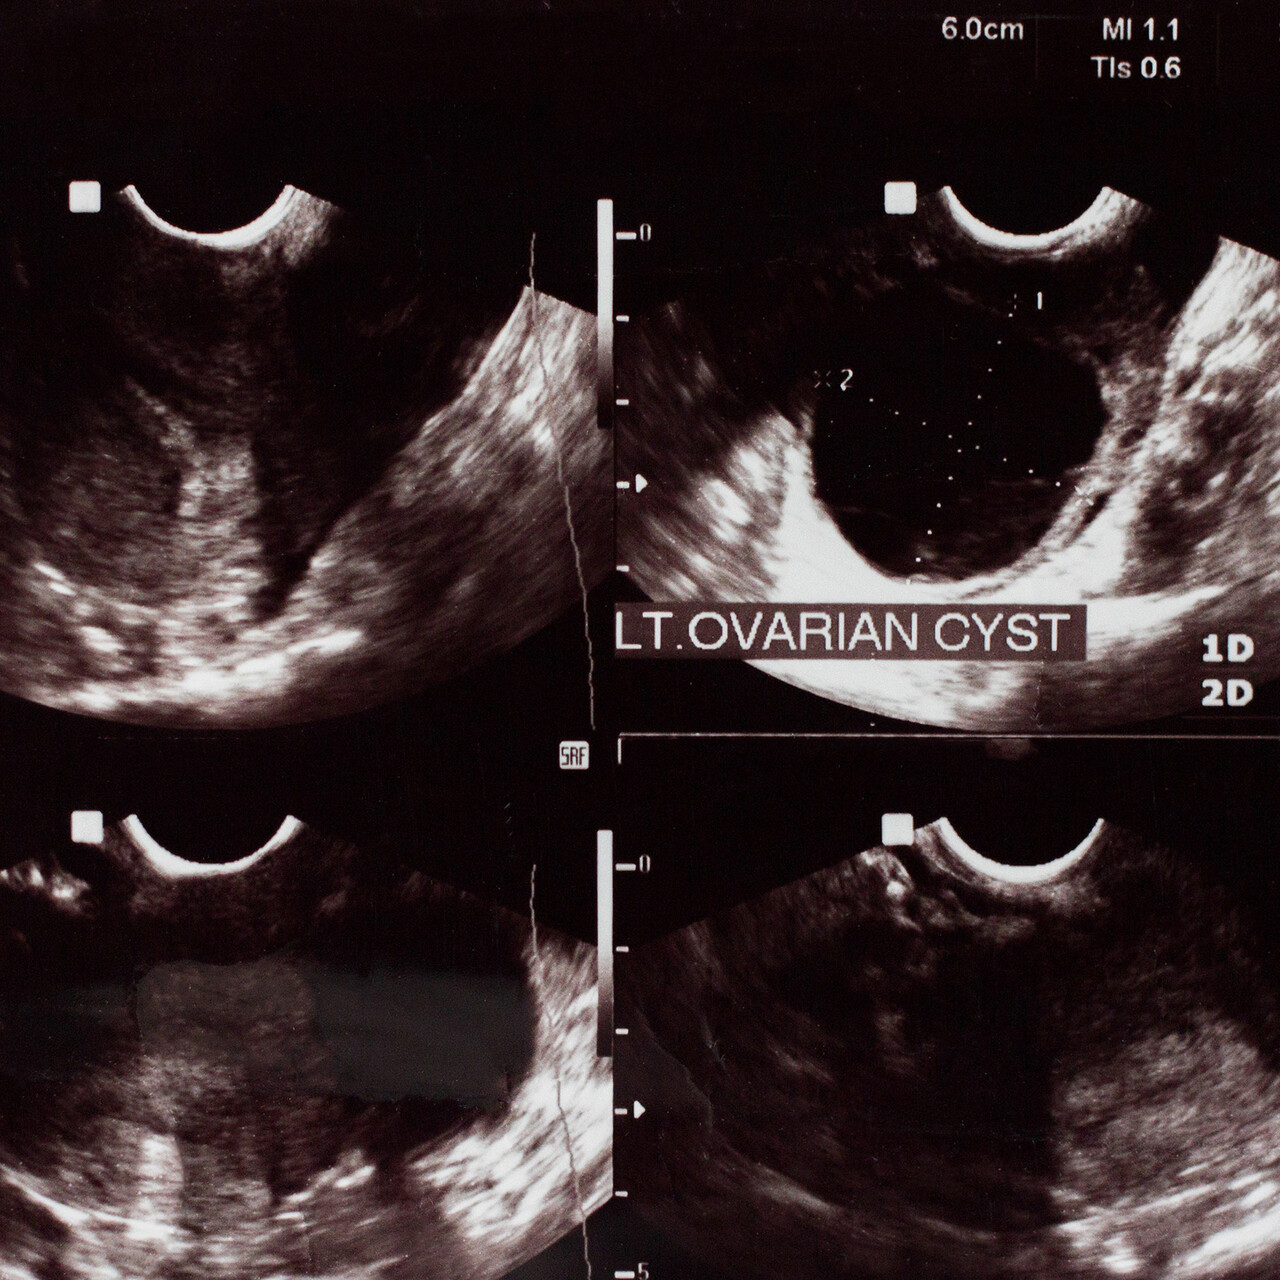

在收集了你的症状的历史之后,你的医生可能会给你开一个超声波蔡康永说。但通常,当涉及到内do时,这些测试不会告诉你太多。蔡博士解释说:“使用血液检测和成像主要是为了排除其他原因,而不是排除子宫内膜异位症。”它们作为诊断工具的作用是有限的,因为“即使在严重的子宫内膜异位症病例中,通常在任何影像学(超声、CT或MRI)上都没有异常发现。”一个例外是,一些有内do的人可能有充血卵巢囊肿她说,要在超声波上显示出来。

蔡医生承认,话虽如此,想为自己所患的疾病取个名字是完全正常的。“但在我看来,并不是每个人都应该通过手术来诊断,因为手术本身并不是没有风险的,”她解释道。但在某些情况下,也可以考虑手术治疗:“如果有明显证据表明卵巢上有异常囊肿,表明子宫内膜异位症,或者一线治疗无效,女性可能会接受手术治疗,”蔡医生说。一线治疗,如激素避孕,旨在减少炎症的内do,每计划生育但在严重的情况下,可能需要手术等其他治疗。